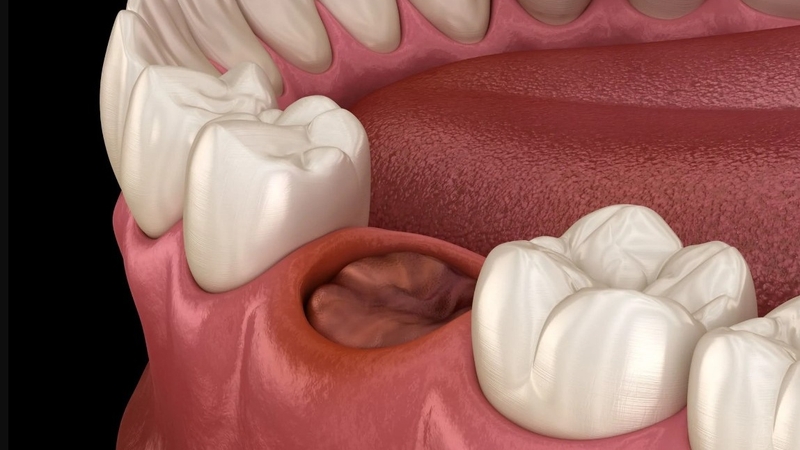

Cục máu đông sẽ hình thành nên khung lưới sợi tế bào, từ đó tạo nên niêm mạch mới có công dụng lấp đầy huyệt ở ổ răng, từ đó hạn chế thức ăn lọt sâu vào ổ răng dẫn đến phát sinh vi khuẩn, gây nhiễm trùng vết thương, viêm nhiễm ổ răng, viêm nướu,... và nhiều tổn thương không đáng có khác. Các mô xương và mô mềm mới cũng được tổng hợp và hình thành dựa trên tác động từ cục máu đông này nên khi thấy có máu đông sau khi nhổ răng, bạn không nên tìm cách loại bỏ chúng ngay lập tức.

Sau khi nhổ răng sẽ để lại ổ răng trống, phần huyệt dưới ổ răng lộ ra ngoài dễ bị thức ăn lọt vào và gây nhiễm trùng không mong muốn. Chính vì vậy việc hình thành cục máu đông sau khi nhổ răng có ý nghĩa quan trọng trong việc bảo vệ phần ổ răng trống này, đặc biệt là huyệt răng. Cục máu đông làm giảm thiểu khả năng viêm xương ổ răng, khô ổ răng,...